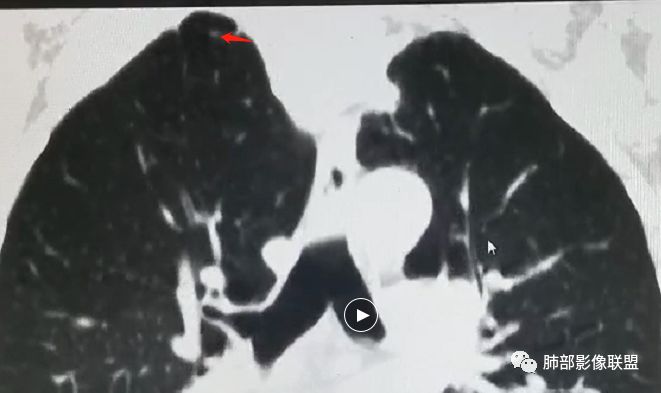

理由:两肺尖都有小结节影(多发)

右肺尖结节边缘可见卫星灶,结节边缘平直凹陷、长毛刺,外观上有炎性结节的特点

彭君:

双肺尖结节 左肺边缘收缩 环形强化 右肺病灶上部边缘平直及长毛刺 下部分边缘膨隆及分叶 细短毛刺 好像有局灶强化 不除外结核基础上的瘢痕癌可能

老年男性,体检发现,右肺上叶尖段类圆形结节

周围有类似小结节